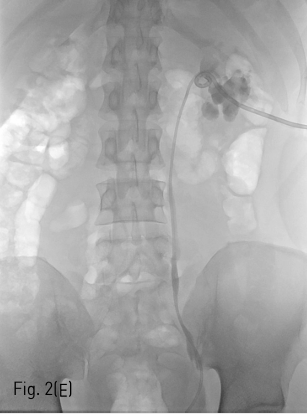

Fig 2E

(E) Nephrostomy catheter was inserted left renal pelvis through neoinfundibulum.

환자는 왼쪽 신장의 isolated calyx에는 8.5Fr. drainage catheter가 insertion 되어 있고 left renal pelvis에는 double J stent가 insertion 되어 있는 상태로 prone position을 취하였다. 기존의 drainage catheter에 0.035inch 유도 철사(Terumo, Tokyo, Japan)를 insertion 하고 catheter는 제거한 후 8Fr. Sheath(Boson, Shrewsbury, USA)를 삽입하였다. 조영제(Visipaque, GE healthcare, Chicago, USA)를 주사하여 tubogram을 시행하였고 isolated calyx 와 콩팥깔때기와의 연결성은 없었다. (Fig.1B) 초음파 유도 하에 21G 천자바늘(Cook, Bloomington, USA)로 isolated calyx를 천자하고 X선 투시하에 천자바늘을 콩팥깔때기에 insertion 되어 있는 double J catheter를 향해 진입시켰다. (Fig. 2A, B) 천자바늘의 속심을 제거한 후 X선 투시하에 조영제를 주사하여 isolated calyx를 지나 콩팥깔때기가 천자된 것을 확인하고 0.018inch 유도 철사(A & A, Gyeonggi, Korea)를 넣었다. (Fig. 2C) 이후 천자바늘을 제거하고 단일 막대 접근 장치(yellow sheath; A & A, Gyeonggi, Korea)를 이용하여 접근로를 확보했다. 유도 철사와 metal stiffening inner cannula를 제거하고 0.035inch 유도철사(Terumo, Tokyo, Japan)를 넣고 6mm x 4cm balloon(Boson, Shrewsbury, USA)을 이용하여 isolated calyx와 콩팥깔때기 간 neoinfundibulum 을 재건하였다. (Fig. 2D) 삽입되어 있는 유도 철사를 통해 isolated calyx, neoinfundibulum 그리고 콩팥깔때기를 차례로 통과하도록 10.2Fr. nephrostomy catheter(Cook, Bloomington, USA)를 위치시켰다. (Fig. 2E) 4일 후 기존의 10.2Fr PCN catheter insertion site를 통하여 10Fr sheath(Terumo, Tokyo, Japan)를 insertion 한 뒤 0.035inch 유도철사(Terumo, Tokyo, Japan)를 방광까지 진입시킨 뒤, 26cm 7Fr double J stent(Boson, Shrewsbury, USA)의 원위부는 방광에 위치시키고 근위부는 isolated calyx에 위치시켰다.(Fig. 3) 이후 isolated calyx로의 접근로에는 10.2Fr. nephrostomy catheter(Cook, Bloomington, USA)를 삽입하고 시술을 종료했다.